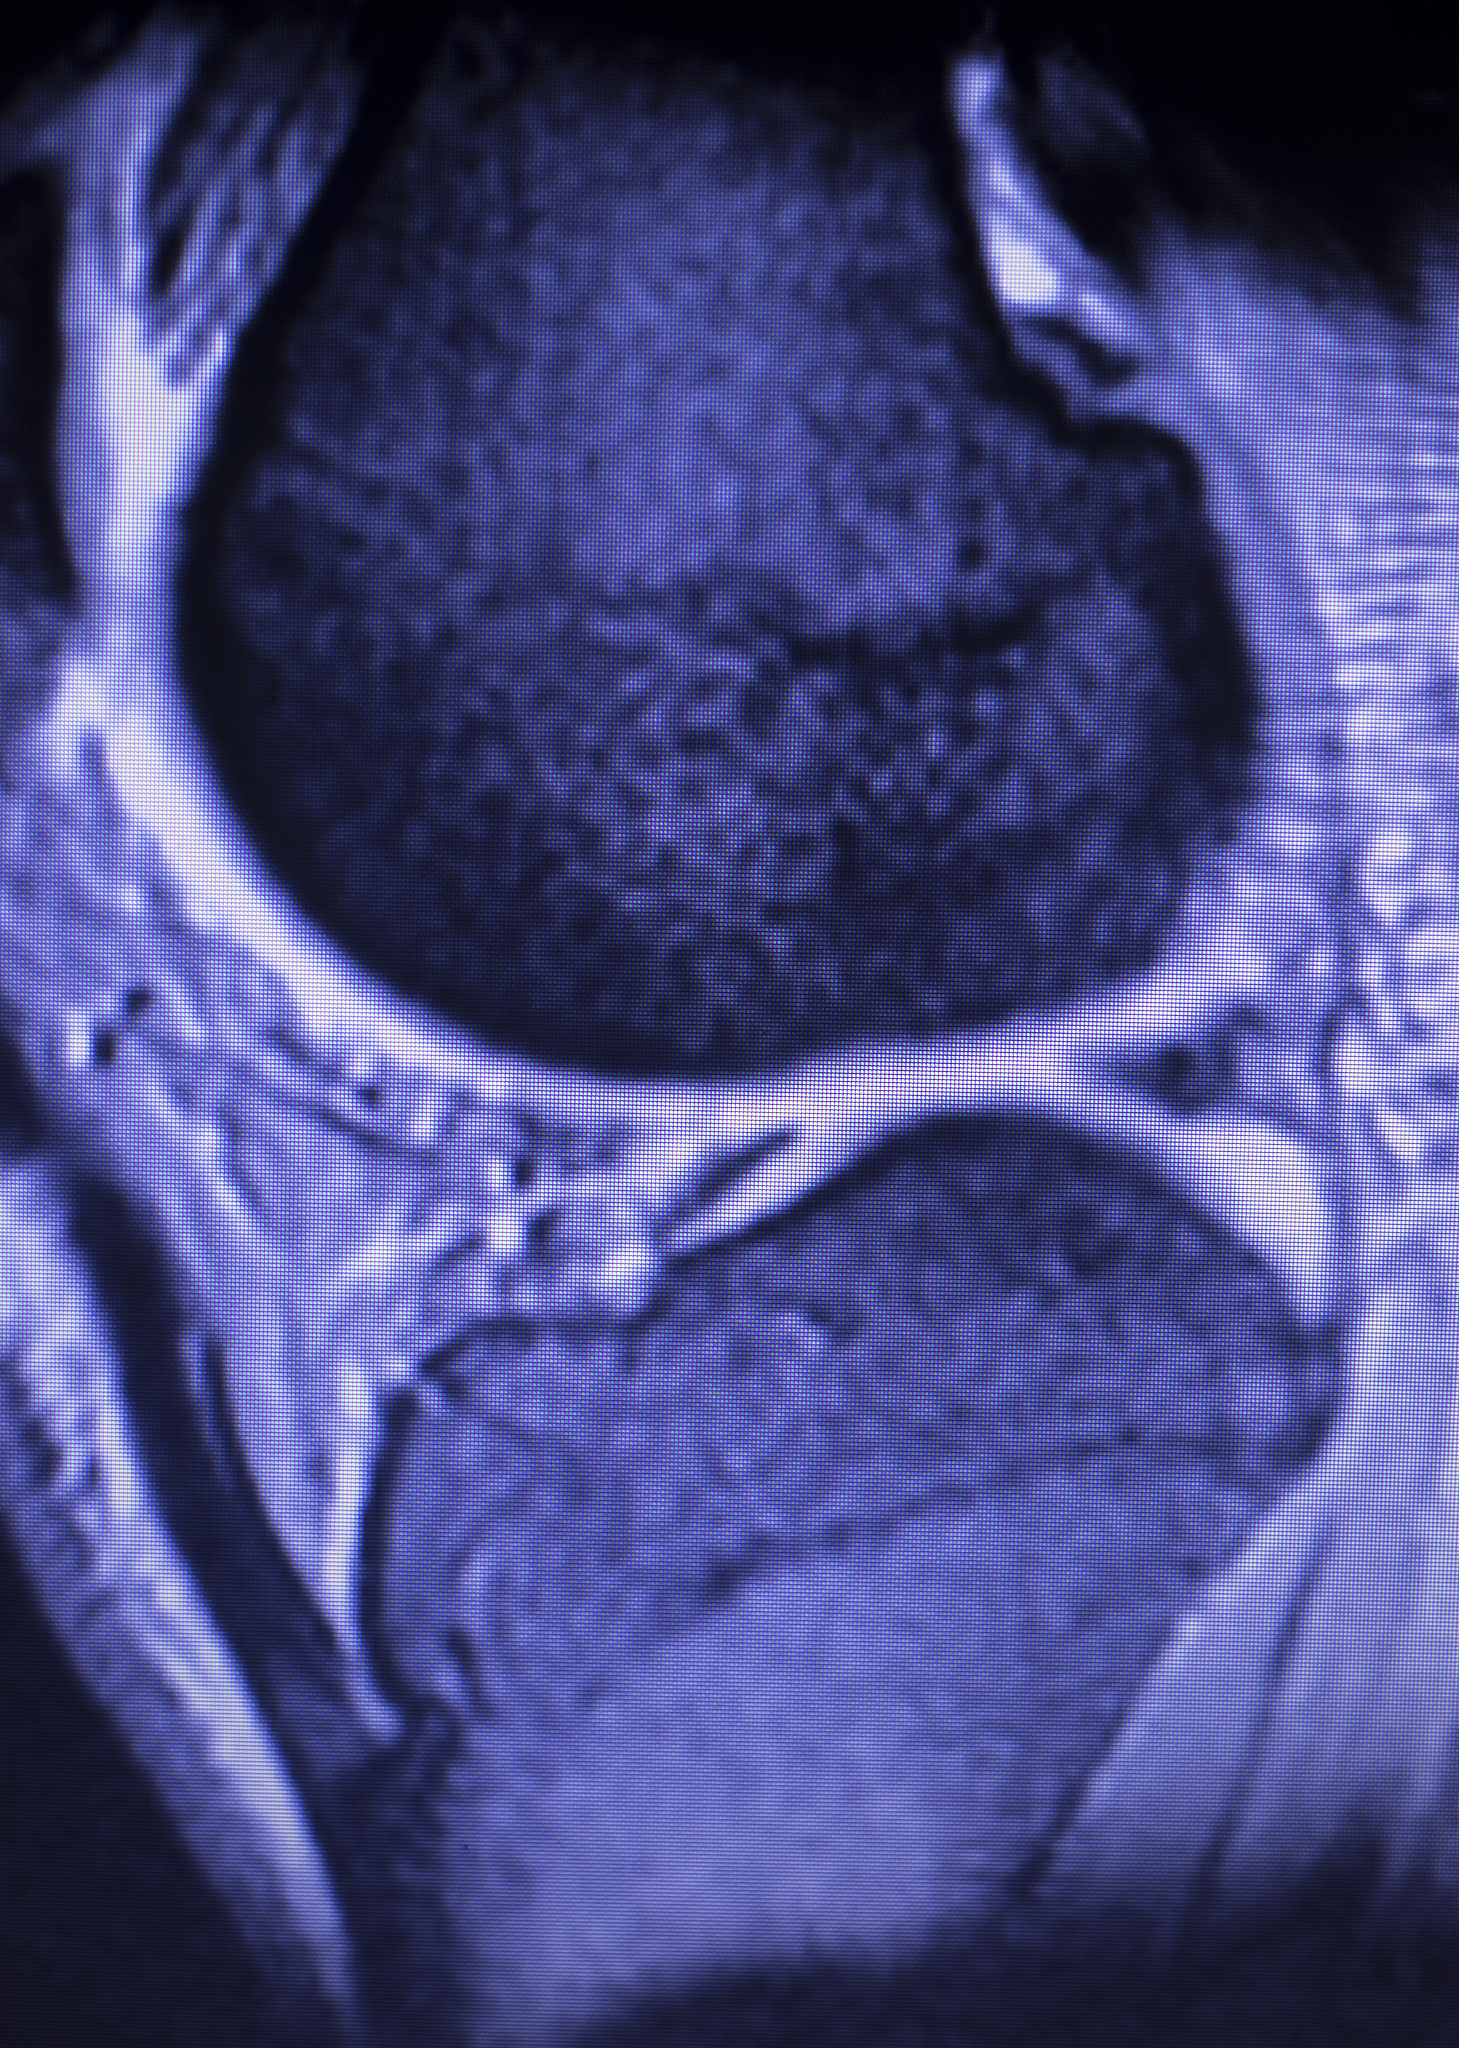

干细胞修复半月板是一种新兴的治疗半月板损伤的方法。干细胞是一种未分化的细胞,它能够分化成各种类型的细胞,包括软骨细胞和骨细胞等。因此,使用干细胞可以促进半月板的修复和再生。